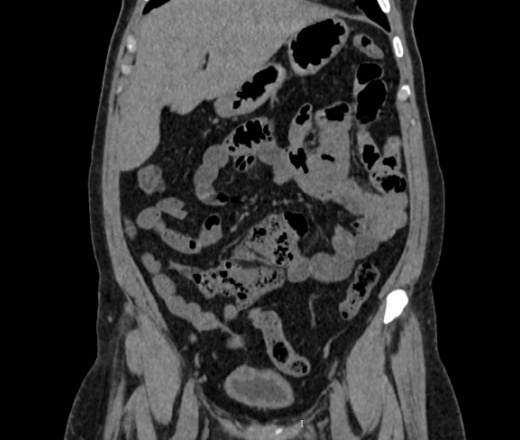

Здравствуйте, женщина 40лет, жалобы на увеличение живота, началось с 2023 года, жалобы на запоры временами и на водянистый стул, подскажите что здесь в области баугиниевой заслонки? инвагинация слепой кишки в подвздошную? что рекомендовать?

В классической рентгенологии такое смещение слепой кишки называли - мобильная слепая кишка.

Описал бы как "кт-признаки болезни Крона (терминальный илеит)", порекомендовал бы колоноскопию с биопсией